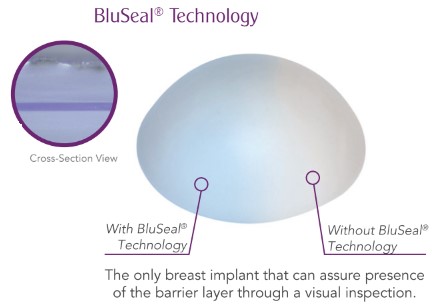

BluSeal

Our BluSeal technology embeds a visually distinct layer of blue silicone into the SilkSurface shell. This patented manufacturing innovation is intended to highlight any imperfections in the barrier layer coverage with a distinct color. This provides the plastic surgeon with the ability to verify whether the barrier layer has coverage defects or other imperfections before implantation that might lead to post-implantation shell rupture or gel bleed. We believe this is another safety innovation that contributes to our substantially lower reported implant rupture rates as compared to reports for our primary competitors.